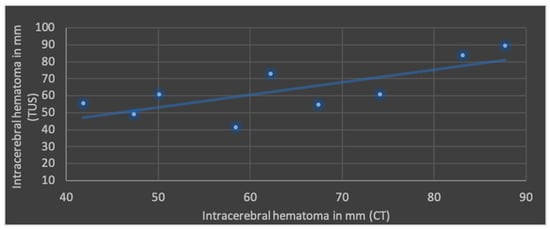

The Pearson’s correlation coefficient (r), including mean values and standard deviation of both modalities in terms of ML shift, lateral ventricular width, subdural space and ICH is shown in Figure 4, Figure 5, Figure 6 and Figure 7.

Figure 7.

Correlation of transcranial ultrasound (TUS) and computed tomography (CT) in terms of intracerebral hematomas (r = 0.74; p < 0.05; mean value TUS: 63.3 ± 15.9 mm; mean value CT: 63.6 ± 16.0 mm).

The best correlation represented by Pearson’s correlation coefficient was shown in ML shift and lateral ventricular width. The evaluation of ICHs in TUS revealed a slightly weaker correlation, but with a p-value below 0.05, still indicating significance at the standard level. No significant correlation was found in terms of subdural space between both modalities; mean values obtained through CT were higher than those in TUS.

Another study by an anesthesiologic department included 30 head-injured patients treated in the ICU. In addition to similar findings regarding ML shift and ventricular width, they also found a strong correlation between the volumes of hyperdense lesions in CT and TUS. However, ischemic areas could not be adequately visualized and there was poor correlation in the volume of late hemorrhagic lesions []. In our study, the depiction of infarcted areas via TUS proved to be challenging. Smaller infarct areas were not always identified (six points on the Likert scale). Similarly, the qualitative evaluation of older hemorrhages showed relatively poor results. Although intracerebral hematomas could be identified, all six investigators considered it demanding to determine the extent and exact boundary of the lesion compared with healthy tissue (especially during the resorption phase and decreasing echogenicity). Interestingly, when comparing the qualitative results of the Likert scale with our quantitative analysis of ICHs, partially contradictory findings emerge. In contrast to the subjectively challenging identification of the extent of lesions, a strong correlation of the maximum diameter measured in TUS and CT was determined. This highlights the need to distinguish between two aspects: identifying the complete boundary of the lesion from healthy brain tissue—which appeared particularly challenging in TUS in our study, especially in cases of resorption edema—and estimating the approximate size of the mass effect itself. It is also noteworthy that the maximum diameters identified in our study suggest larger intracerebral hematomas compared with those reported by Caricato et al., which may also influence comparability [,].

Transcranial ultrasound is a safe, cost-effective, and time-efficient method that may become increasingly relevant for imaging post-hemicraniectomy patients. In our experience, transcranial ultrasound was effective in visualizing intraventricular catheter placement, the ventricular system, midline and space-occupying lesions. The present study showed a strong correlation in terms of midline shift, lateral ventricular width and intracerebral hematomas between computed tomography and transcranial ultrasound. Further enhancements in image quality could potentially reduce the overall need for CT scans.